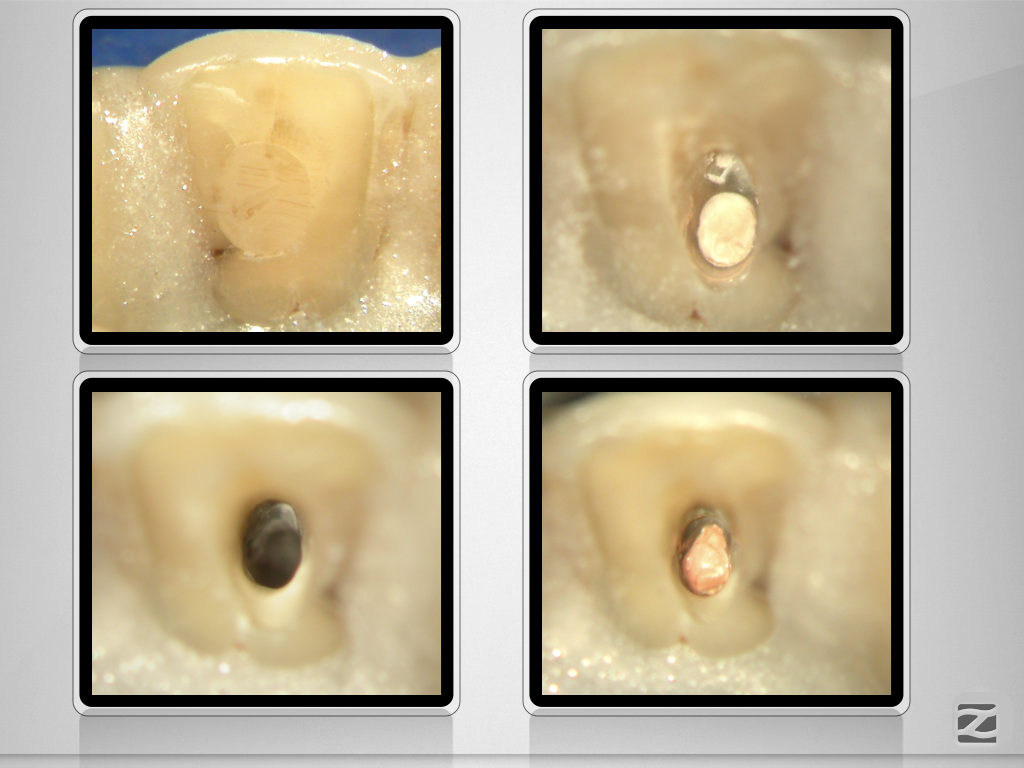

12D.002

Unterfüllt & überextendiert